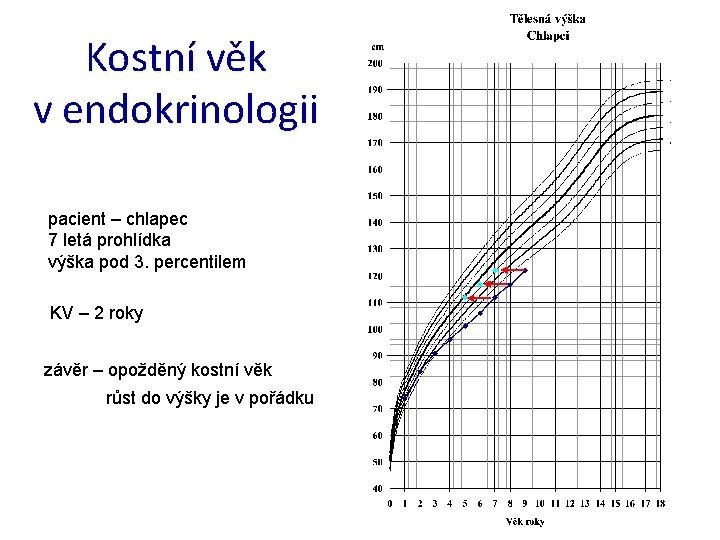

Kostní věk I • ukazatel biologického věku, určuje stupeň zralosti kosti • zjišťován na základě RTG snímku ruky a distální části předloktí levé HK • nejčastější metody: – Greulich-Pyle • porovnání rentgenogramu s fotografickými standardy – Tanner-Withause (TW 1, TW 2, TW 3 – 2001) • hodnocení tvaru, velikosti osifikačních center 20 kostí a jejich vzájemného vztahu (RTG z 76 cm) • R, U, MTC I. , III. a V. , ph. prox. I. , III. a V. , ph. med. III. a V. , ph. dist. I. , III. a V. , ossa carpalia 7

Kostní věk II kostní věk: 3 roky 11 let 16, 5 roku

Kostní věk v endokrinologii pacient – chlapec 7 letá prohlídka výška pod 3. percentilem KV – 2 roky závěr – opožděný kostní věk růst do výšky je v pořádku